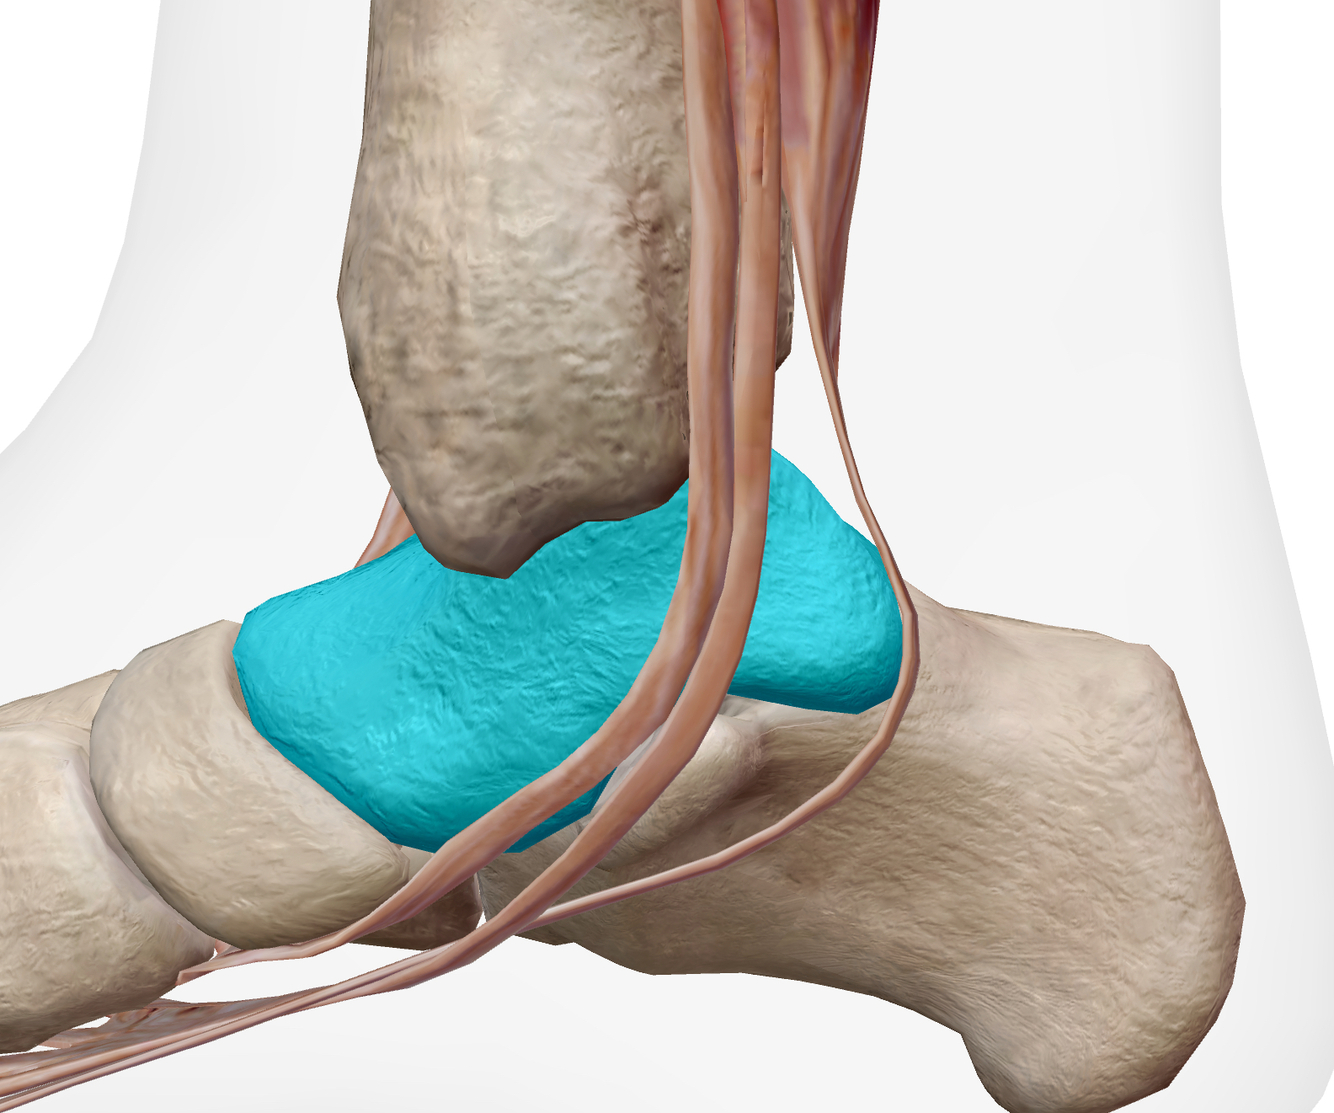

Q

Identifier les structures sur cette image.

Indice: On y voit les os suivants : Tibia, talus et calcanéus

A